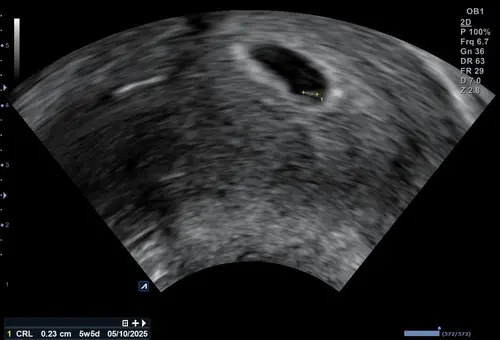

Ongeveer 5w5d en een kloppend hartje 🥰